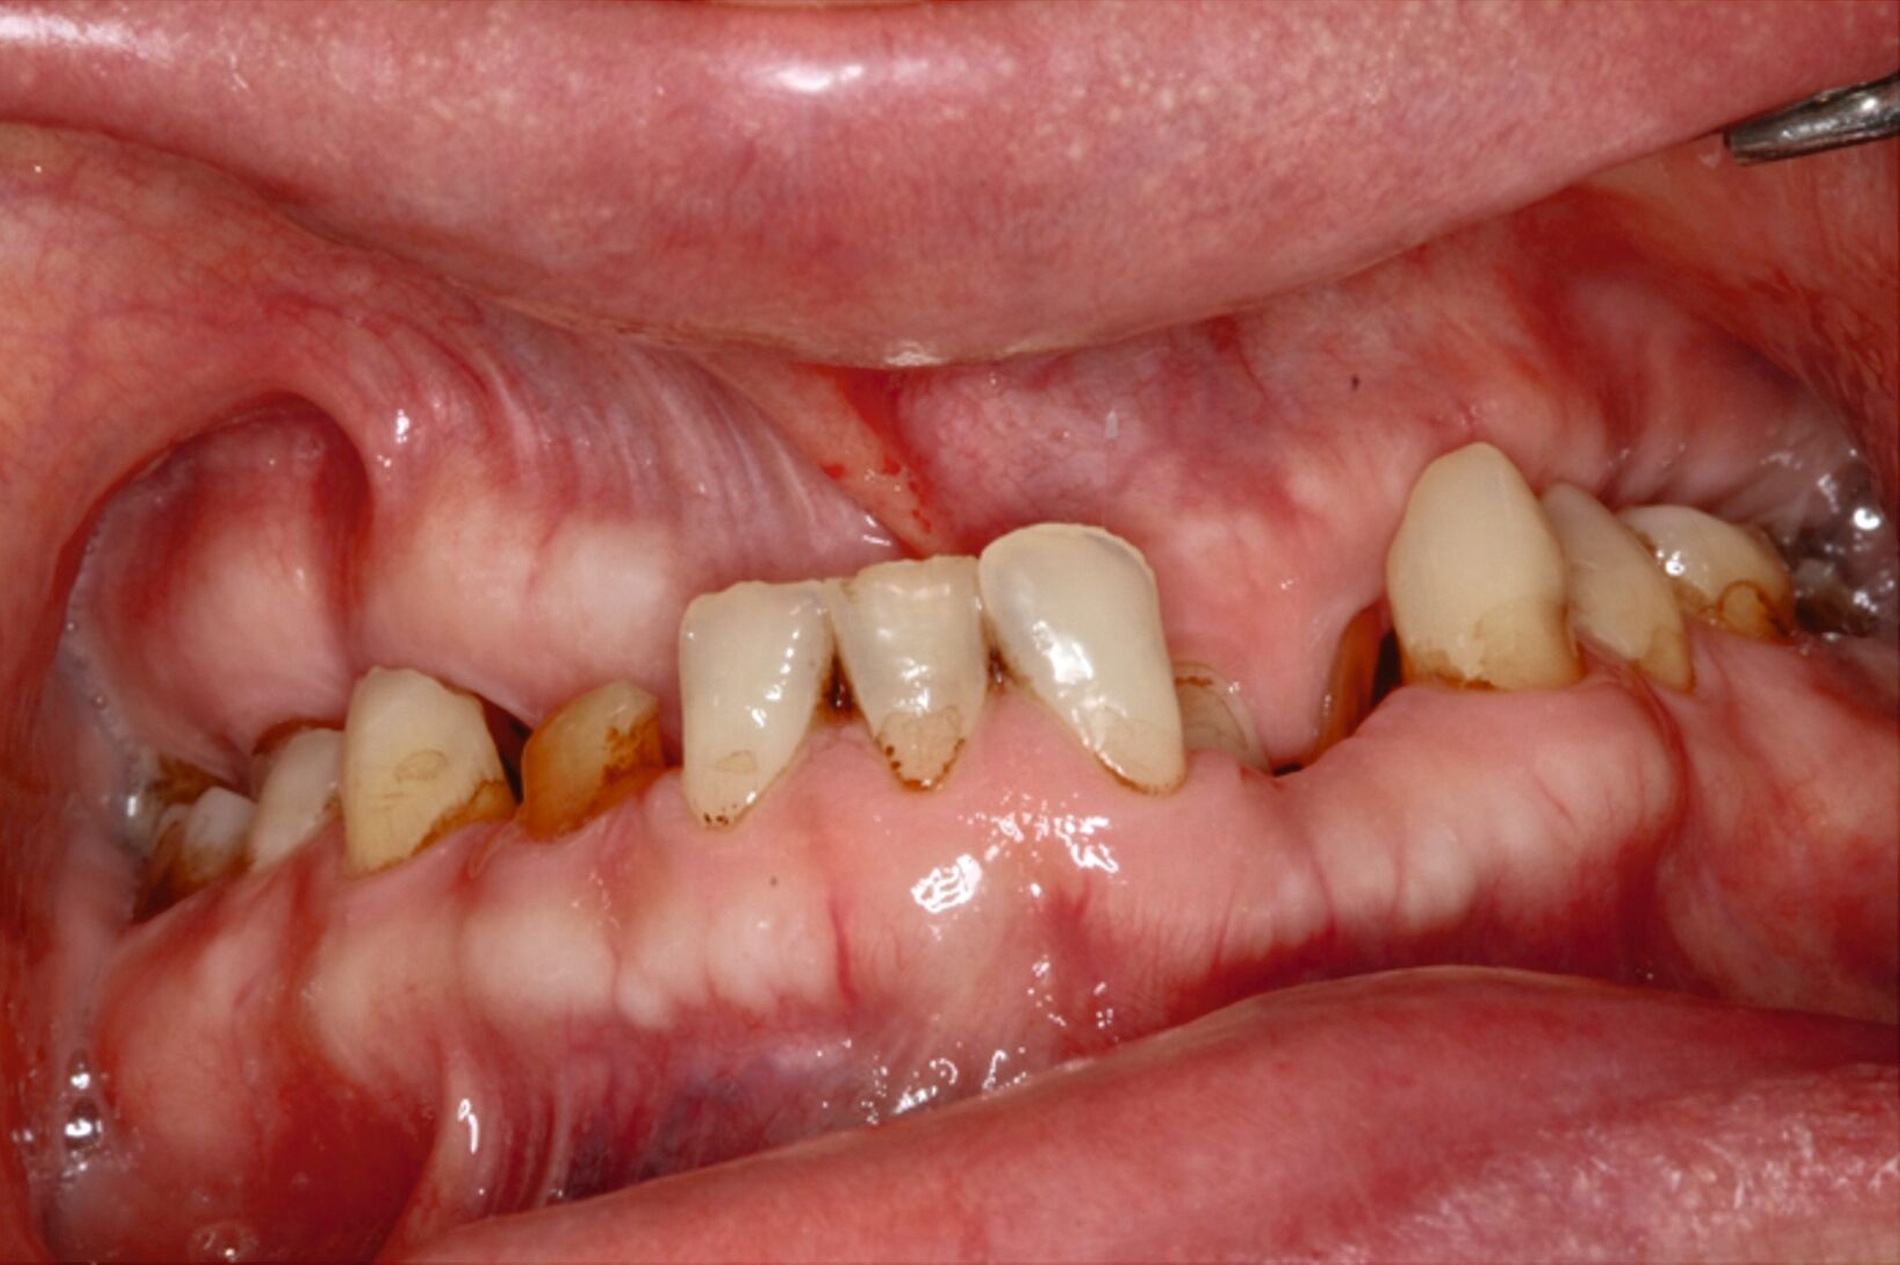

Ein 30-jähriger Patient stellte sich mit multipler Oligodontie (15 fehlende bleibende Zähne), Persistenz von Milchzähnen sowie ausgeprägter Dysgnathie mit progenem Deckbiss vor. Klinisch zeigten sich hypoplastische Restzähne, Fehlstellungen und erhebliche funktionelle Beeinträchtigungen (Abbildung 1). Sein Wunsch bestand in einer möglichst optimalen ästhetischen und funktionellen Versorgung seiner für ihn äußerst unbefriedigenden Gebisssituation. Die molekulargenetische Analyse bestätigte eine homozygote Mutation im WNT10A-Gen als Ursache der Zahnagenesie.